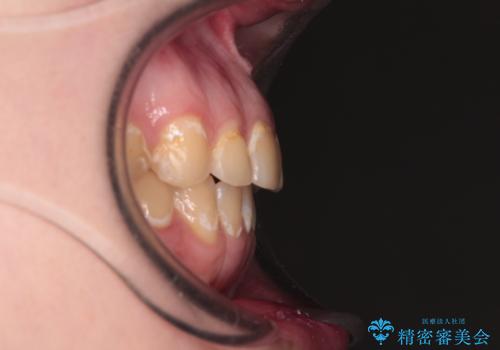

- 前歯のデコボコとクロスバイトが気になり、インビザラインによる矯正治療を希望して来院された患者様です。

上顎側切歯(上の真ん中から2番目の歯)が舌側転位している場合、無理して動かそうとすると歯髄壊死を起こすリスクが高い印象があります。

インビザライン単体でも治療は可能ですが、安全策としてインビザラインで歯列を移動する前に上顎前歯をワイヤー矯正で整え、その後上下歯列をインビザラインにて矯正治療を行うこととしました。

舌側転位している側切歯特有の、切縁の位置が不揃いであったり、根元が内側に引っ込んだ状態であったりという、インビザライン独特の仕上がりになることなく、きれいに整った歯列とすることができました。